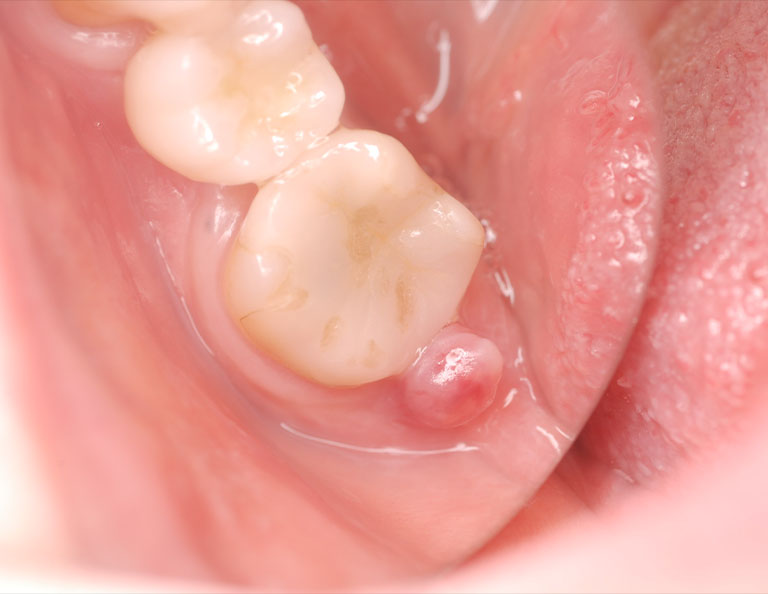

初診時の状態です。歯肉に腫脹が認められます。

被せ物を外すと歯の神経である歯髄は死んでしまっており、歯に亀裂も認められます。

亀裂を樹脂で補強し、ラバーダム防湿下で根管治療を開始しました。

状態が改善したことを確認し、最終的な被せ物を装着しました。